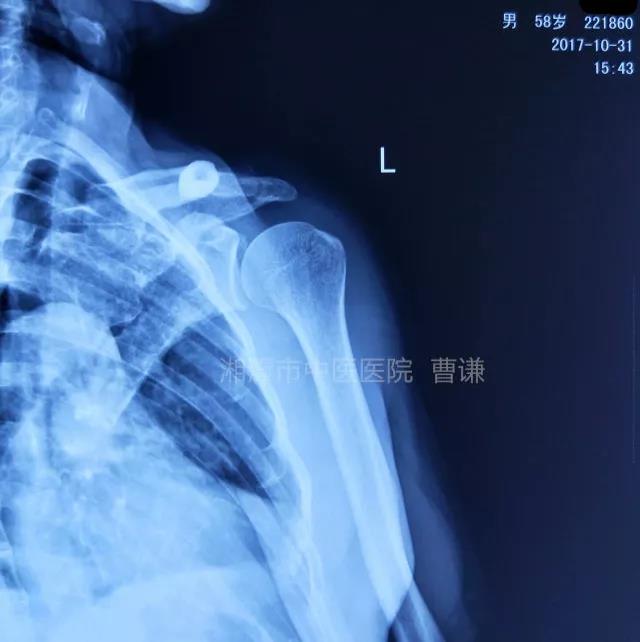

当地接诊医生应该说还是很负责的,同时拍了健侧片对比:

影像科报告,骨科医生光看报告行吗?